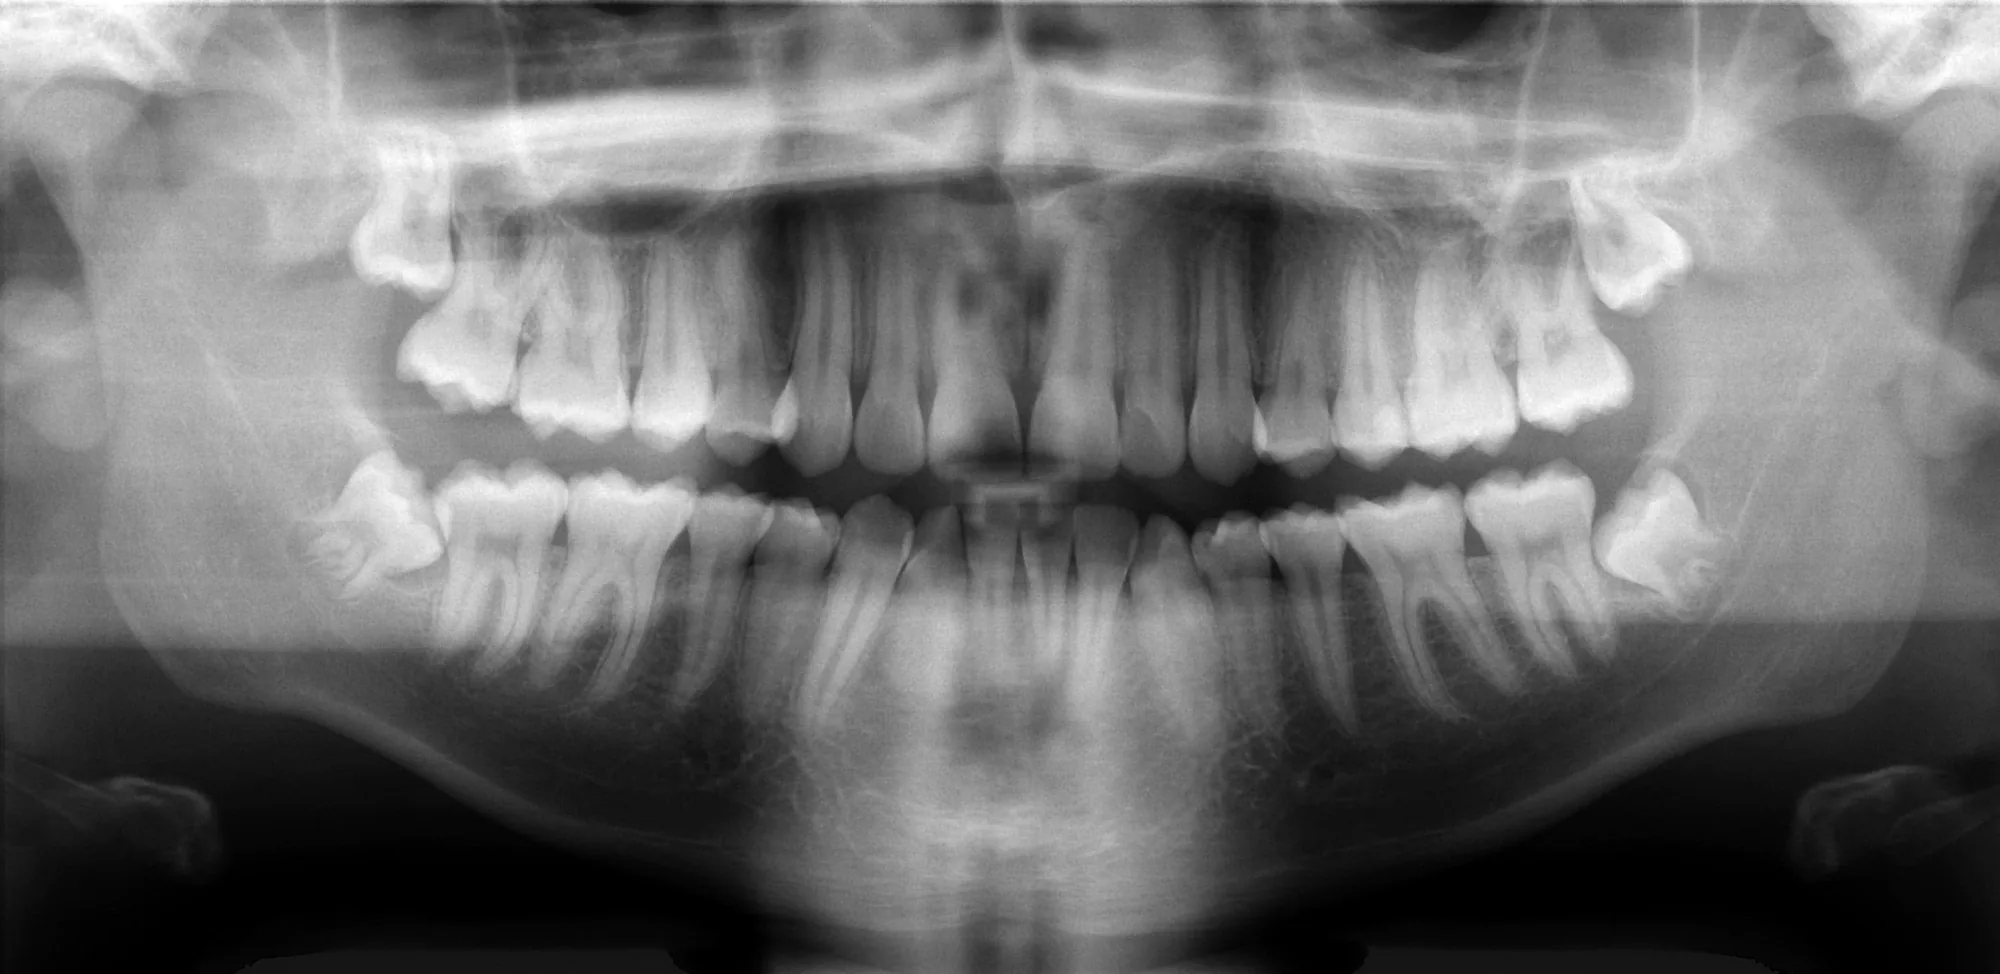

Radiografia Panorâmica

A radiografia panorâmica é um exame de imagem que proporciona uma visão ampla de toda a cavidade bucal em uma única tomada, permitindo a avaliação simultânea das arcadas superior (maxila) e inferior (mandíbula), além das estruturas adjacentes.

Por meio deste exame, é possível identificar alterações como lesões cariosas extensas, reabsorções ósseas e radiculares, granulomas, cistos, tumores, dentes inclusos/impactados e fraturas decorrentes de traumas.

Trata-se de um exame extraoral, rápido, confortável e de baixa exposição à radiação, frequentemente solicitado como exame inicial para planejamento de tratamentos, acompanhamento da saúde bucal e como exame pré-operatório.

Radiografia Panorâmica

A radiografia panorâmica oferece uma visão ampla e completa de todas as estruturas bucais em uma única imagem. Fundamental para avaliação odontológica geral.

Qual a diferença entre radiografia periapical e panorâmica?

A radiografia periapical é intraoral e mostra de 1 a 4 dentes em alta definição, sendo ideal para diagnóstico de canais, lesões cariosas e granulomas.

A panorâmica é extraoral e mostra todas as arcadas, mandíbula, maxila e ATM em uma única imagem, sendo usada para visão geral, planejamento ortodôntico e identificação de dentes inclusos.